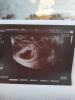

Во-вторых, я сегодня наконец-таки сходила на первое УЗИ. 8 недель и 3 дня))) Я даже могу сказать четко день зачатия. День когда мой муж вернулся с полей после 2 недель пребывания там))))

P. S.: мое счастье уже 18,7 мм)))